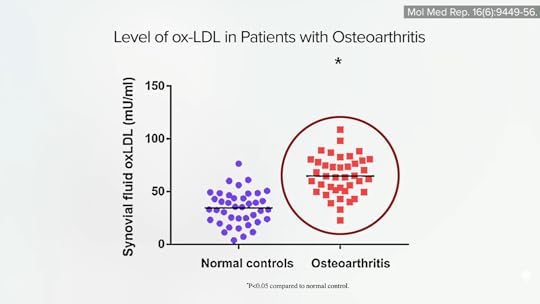

Osteoarthritis develops when the cartilage that lines and cushions our joints breaks down faster than our body can build it back up. Our knee is the most commonly affected joint, leading to the assumption that the association with obesity was simply due to the excess wear and tear from the added load on the joints. But non-weight-bearing joints, like our hands and wrists, can also be affected, suggesting the link isn’t “purely mechanical.” Obesity-related dyslipidemia may play a role, with elevations in the amounts of triglycerides, fat, and cholesterol in the blood aggravating inflammation in the joints, just like cholesterol can exacerbate the inflammation in our artery walls.

Osteoarthritis sufferers not only have higher cholesterol levels in the blood, but they also have them within their joints, as you can see below and at 1:52 in my video The Best Knee Replacement Alternative for Osteoarthritis Treatment, in aspirated joint fluid and also found in the cartilage itself.

When cholesterol is dripped onto human cartilage in a petri dish, the inflammatory degeneration worsens, which helps explain why the higher our cholesterol, the worse our disease, as shown below and at 2:05.